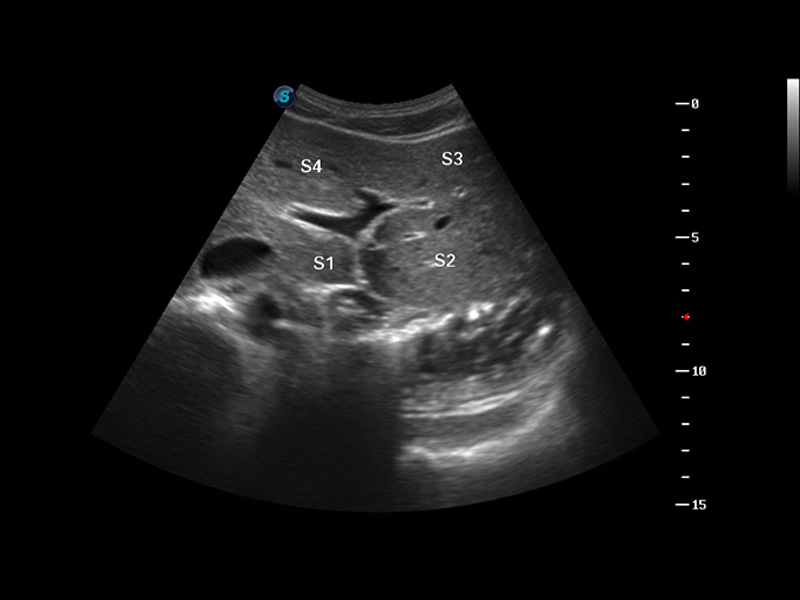

S8 EXP便携式彩色多普勒超声诊断仪是狗万官方网站研发的高端全身应用型便携彩超。高通道的VIS平台融合可视化(Visual)、智能化(Intelligent)和人性化(Smart)的特点,配以狗万官方网站自主研发生产的探头大家族,使您能够快速、准确的获得病人信息,提高工作效率的同时减轻疲劳。

谐波成像

空间复合成像